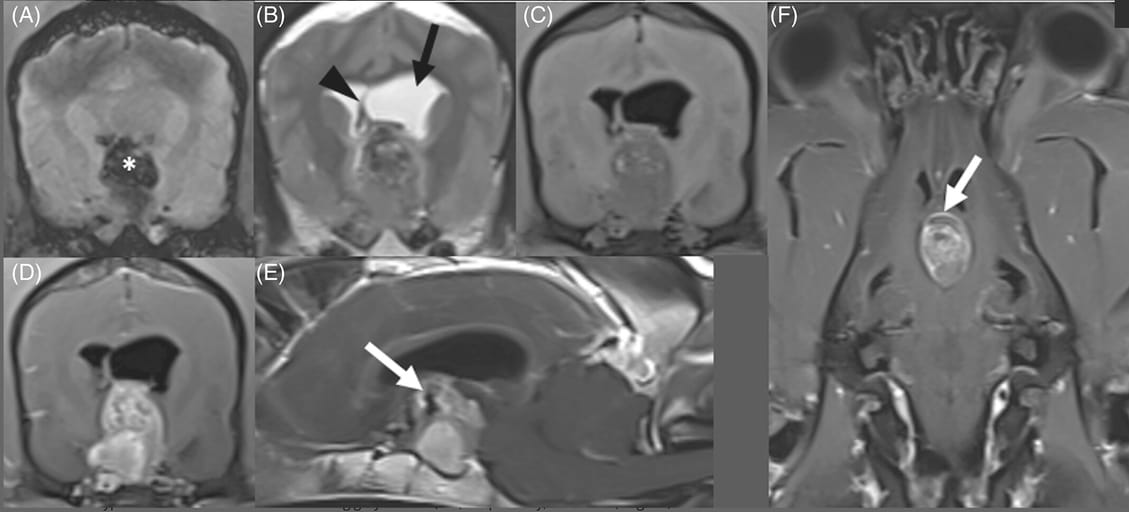

Magnetic resonance imaging of pituitary apoplexy in the same dog. (A) Transverse susceptibility-weighted imaging (SWI) reveals a large suprasellar blooming artifact (marked with white asterisk). (B) Transverse T2-weighted (T2W) image revealing an ovoid suprasellar mass which is heterogeneously T2 hypointense with internal T2 hyperintense foci relative to surrounding gray matter. Obstructive hydrocephalus of the left lateral ventricle is marked with the black arrow, with deviation of the septum pellucidum (black arrowhead), consistent with a falcine shift. (C) Transverse T1-weighted (T1W) image heterogeneously T1 hypointense with internal T1 hyperintense foci relative to surrounding gray matter. (D-F) Respectively, transverse, sagittal, and dorsal T1W images after contrast administration, showing strong contrast-enhancement with some areas of ring-enhancement (white arrows). There is flattening of the rostral cerebellum and compression of the rostral colliculi, consistent with transtentorial herniation.